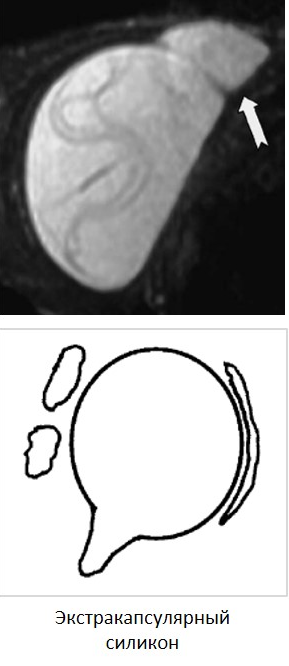

Экстракапсулярный разрыв приводит к попаданию физиологического раствора или силиконового геля в окружающие ткани. Экстракапсулярный разрыв также подразумевает внутрикапсулярный разрыв.

Рис.1.  Экстракапсулярный разрыв справа, экстракапсулярное распространение силикона (зеленым). А – T2-ВИ, аксиальная плоскость, «знак слезы» (розовым). B – T2-ВИ, корональная плоскость, подкапсулярная линия (коричневым). С – аксиальная плоскость, Silicon Only (последовательность, чувствительная к силикону, с подавлением МР сигнала от окружающей ткани молочной железы) - визуализация распространения силикона в мягкие ткани.